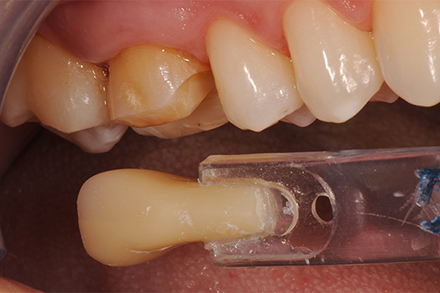

Shade selection